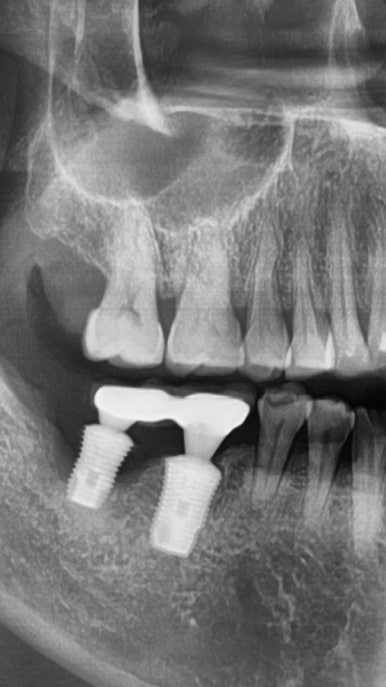

2."임플란트 뿌리부분이 쓰다보니 찢어져서 머리부분도 빠져버렸어요."

다른치과에서 몇년전에 한 인플란트가 흔들리고 붓는다고 온 분이었습니다.

그림에 1로 표시한 부분은 임플란트 주변을 감싸는 뼈가 많이 녹아서 흔들리고

2로 표시한 치아는 중간 연결고리나사가 부러져서 임플란트 머리도 같이 흔들리는 상태였습니다.

1과 2 임플란트 모두 제거하고

새로 임플란트를 심어 완성하였습니다.